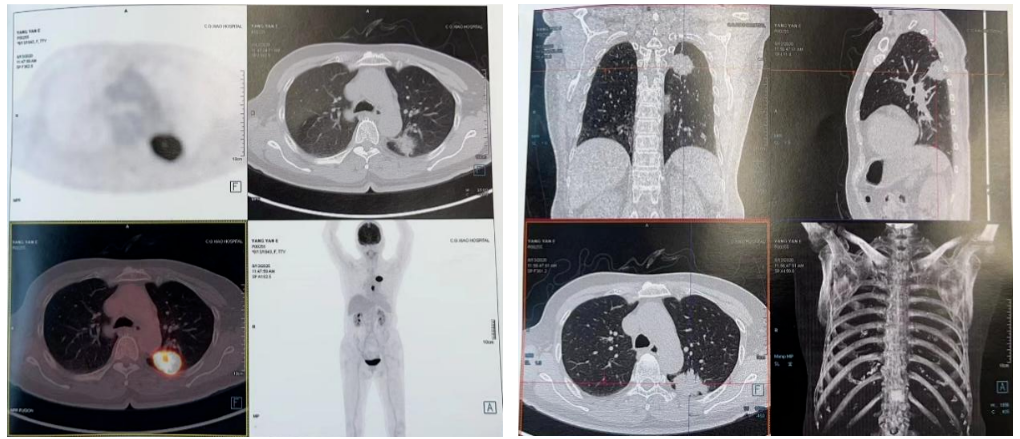

PET-CT(2020-08-13):食管胸下段管壁不均匀增厚,见放射性摄取增高,大小约18×14×27mm,SUVmax 14.6,符合食道癌表现。右侧肺门及纵隔(4R、5、7区)可见多个稍肿大淋巴结,最大约8×5mm,考虑炎性淋巴结可能性大。

左肺上叶尖后段团块状密度增高影,PET见放射性摄取增高,大小约40×29×31mm,SUVmax 28.0。病灶跨越左侧斜裂胸膜生长,密度均匀。左肺上叶胸膜下可见多发微小结节状密度增高影。建议治疗后复查,必要时活检排外恶性肿瘤的可能。

胸部平扫+增强CT(2020-08-27):食道中段管壁增厚,上下累及约4.5厘米(约胸5/6椎间隙水平至胸8椎体上缘水平),增强后可见轻度强化,隆突下见境界不清淋巴结。左肺上叶尖后段及相邻左肺下叶背段交界处见团块状直径约2.5厘米软组织密度灶,边缘可见毛刺,左侧胸腔积液,左下肺膨胀不全。右肺下叶见少许条状影。结论:1、食管癌。2、左肺上叶尖后段病灶,符合肺癌。左侧胸腔积液,左下肺膨胀不全。

2021-10-28外院PET-CT:原食管胸下段管壁高代谢灶较前缩小,放射性较前减低,现大小约15×17×17mm,SUVmax 3.1,考虑为治疗后改变。左肺上叶团块状高代谢灶较前缩小,放射性摄取较前减低,现大小约25×18mm,SUVmax 2.1,考虑为治疗后改变。

2022-03-28 PET-CT:1、食管癌放化疗后,食管胸中段管壁不规则增厚伴结节状代谢增高,与上次(2021-10-28)PET/CT检查对比,病灶代谢较前明显增高,考虑为肿瘤复发病灶。2、左肺癌放疗后及靶向药治疗后,原左肺上叶团块状高代谢“肿瘤灶”,现范围较前稍缩小,代谢较前稍减低,考虑为治疗后改变(肿瘤完全活性受抑,伴少许炎性反应可能)。